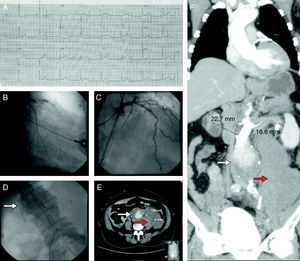

(Panel A) Electrocardiogram showing ST-segment elevation in leads V1–V4 compatible with an anterior myocardial infarction. (Panel B) Coronary angiography showing acute stent thrombosis in the proximal segment of the anterior descending coronary artery. (Panel C) Coronary angiography after thrombus aspiration showing reestablishment of TIMI 3 flow in the anterior descending coronary artery. (Panel D) Aortography revealing an abdominal aneurysm with slow flow and subtraction images suggestive of thrombus (white arrow). (Panels E and F) Computed tomography imaging showing a ruptured abdominal aneurysm (white arrow) surrounded by a large retroperitoneal hematoma (red arrow).

Case reportA 68-year-old man with hypertension, dyslipidemia and ischemic heart disease, with a previous infarction in 2001 when he underwent percutaneous angioplasty of the anterior descending coronary artery, presented at our emergency room with shock, after being found at home unconscious. The patient was confused but was able to report abdominal/dorsal pain (poorly localized) previous to the syncope. The electrocardiogram showed an anterior myocardial infarction (Figure 1, panel A) and the echocardiogram confirmed impaired contractility in the anterior descending artery myocardial territory. Along with fluids and pharmacological therapy, the patient underwent coronary angiography that revealed acute stent thrombosis in the proximal segment of the anterior descending coronary artery (Figure 1, panel B). TIMI 3 flow was reestablished immediately after thrombus aspiration (Figure 1, panel C). Arterial access was obtained via the femoral artery and during the progression of the catheter an abdominal aorta enlargement was suspected. The aortogram confirmed the presence of an abdominal aneurysm with slow flow and subtraction images suggestive of thrombus (Figure 1, panel D, arrow). Computed tomography was promptly performed and confirmed the presence of a ruptured abdominal aneurysm (Figure 1, panels E and F, white arrows) surrounded by a large retroperitoneal hematoma (Figure 1, panels E and F, red arrows). The patient underwent urgent vascular surgery with successful immediate results. The postoperative period was long with multiple complications (infection and abdominal reintervention for correction of bowel perforation due to ischemic colitis). Despite the severity of the initial clinical picture and subsequent complications, all of the latter were promptly and completely resolved and the patient was discharged asymptomatic after 43 days of hospital stay. At nine-month follow-up he was asymptomatic, with preserved left ventricular ejection fraction, completely autonomous and in good general health. This case report highlights the need to observe the patient as a whole, and demonstrates that good results can be achieved, even in serious medical conditions, with expert diagnosis and immediate treatment.